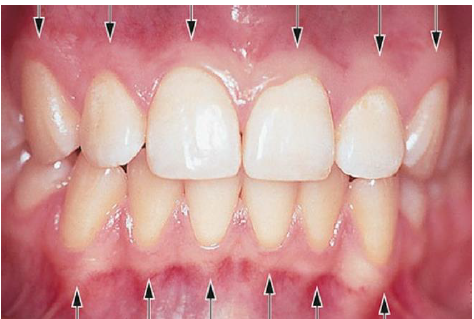

Com auxilio da figura abaixo, assinale a alternativa correta a respeito das proposições de I a IV.

I - A gengiva é a parte da mucosa mastigatória que cobre o processo alveolar e circunda a porção cervical dos dentes.

II - A gengiva consiste em uma camada epitelial e um tecido conjuntivo subjacente, chamado de lâmina própria.

III - A gengiva assume sua forma e textura definitivas em associação com a formação dos dentes. Em direção à coroa, a gengiva de cor rósea termina na margem gengival livre, que possui um contorno festonado.

IV - No sentido apical, a gengiva é contínua com a mucosa alveolar, que é frouxa e de cor vermelha mais escura, da qual em geral é separada por uma linha limitante facilmente reconhecida, chamada de junção mucogengival.